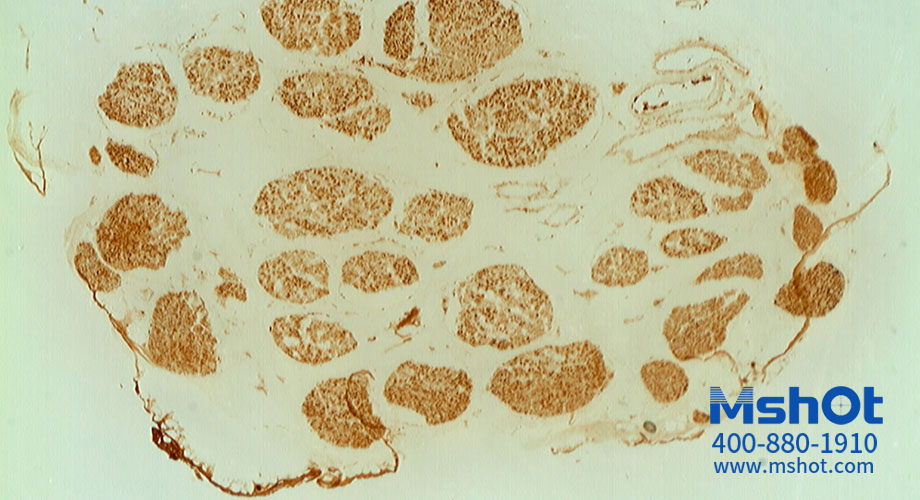

神經(jīng)纖維切片顯微圖片。 (操作提示:點(diǎn)擊圖片或使用鍵盤上的方向鍵來轉(zhuǎn)換要查看的圖片)